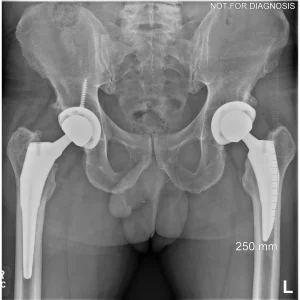

A total hip replacement (also called total hip arthroplasty) is a surgical procedure in which a damaged or worn hip joint is replaced with artificial components. The hip is a ball-and-socket joint, meaning the ball at the top of the thigh bone sits in a socket on the pelvis. During surgery, the damaged ball (femoral head) is replaced with a metal or ceramic ball attached to a stem, and the damaged socket is replaced with a metal cup lined with plastic, ceramic, or metal.

- The surgeon removes the damaged bone and cartilage and inserts the artificial joint